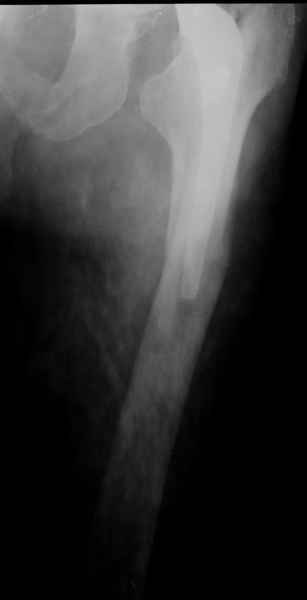

Уважаемые коллеги, продолжая дискуссию, начатую на "Вреденовских чтениях", хочу сказать, что принципиально сущестует два возможных варианта лечения.

1.Остеосинтез на ножке. Мне кажется, что применительно к этому случаю малоперспективный вариант. Синтез хорош, когда можно его выполнить в малоинвазивном исполнении и достигнуть стабильности. Действительно, если ножка б/цементной фиксации после этого не будет иметь фиксации, то ревизия не будет иметь проблем. В представленном случае стабильность синтеза сомнительная, а проведение доп.иммобилизации приведет к контрактуре суставов.

Хочется показать два подобных случая, П-ка З. 72 лет и п-т Г. 80 лет. Сразу принимаю замечание, что это были ножки цементной фиксации, просто под руками не было бесцементника.